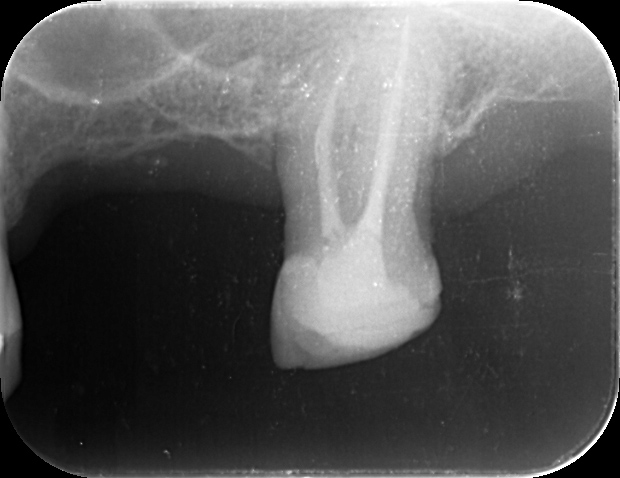

下の写真は、マイクロスコープで見た根管の様子です。いかに治療の精度が高まるか、一目瞭然だと思います。